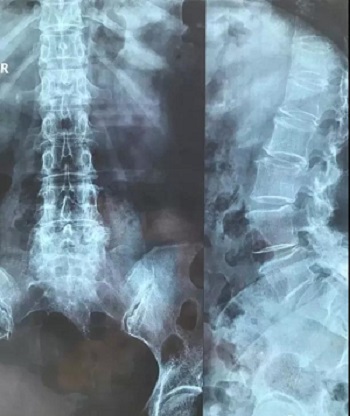

八、拍片子时,如果一张片子上有两张图像的时候,合起来拍一张,分开再各拍一张(如以下三张)

十二、拍摄时,尽可能的将片子上的文字信息拍摄清楚,并将左右拍摄清楚(片子上有标R,表示右侧right,L, 表示左侧left的意思), 每张片子上的文字都能按照阅读习惯拍正确,不要拍反了。

拍摄时,必须要对着片子上的文字对焦, 方向正确,将文字拍摄得清晰可视,保证放大图片后文字依然清晰可见(如下图),尽可能多的保留片子上的信息。